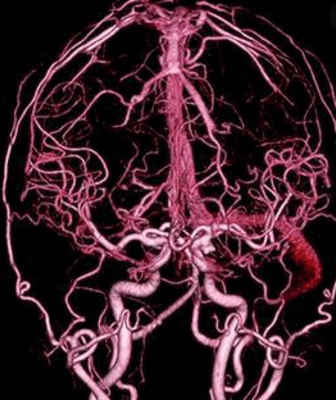

Целью селективной церебральной ангиографии при SP является исключение другой сосудистой патологии, характеризующейся артериовенозным шунтированием, а при обнаружении SP - подробное изучение его ангиоархитектоники, идентификация всех венозных коллекторов, соединяющих синус и экстракраниальное образование [1, 25]. В редких случаях проводится венография путем прямой пункции образования [46, 49]. Проведенная селективная церебральная ангиография больному М. позволила верифицировать SP.

Виртуальная ангиография головного мозга в медицинских центрах Санкт-Петербурга осуществляются с помощью двух типов томографии:

С помощью КТ и МР ангиографии врачи детально могут исследовать группу экстракраниальных и интракраниальных сосудов головного мозга и выявить патологии на ранней стадии. Обследованием состояния вен головы занимается КТ и МР венография - одно из новых и инновационных направлений томографических технологий. Вены головного мозга очень долго время в медицине не оценивались, поскольку не было достойного диагностического метода их визуализации. Поэтому роль различных расстройств венозного кровообращения в этимологии болезней головного мозга продолжительный период сильно недооценивалась. Появление в последние 10 лет специальных ангиопрограмм МРТ и КТ, нацеленных на нейровизуализацию именно вен, значительно облегчило специалистам задачу выявления патологий и аномалий в этой области.

Как КТ ангиография, так и МР ангиография головного мозга весьма информативны. Считается, что КТ сосудов головного мозга лучше покажет аневризмы и нарушения кровообращения в острой фазе и сосудистые нарушения после ЧМТ. На МРТ сосудов головного мозга будет лучше всего видны деформации магистральных сосудов головы.